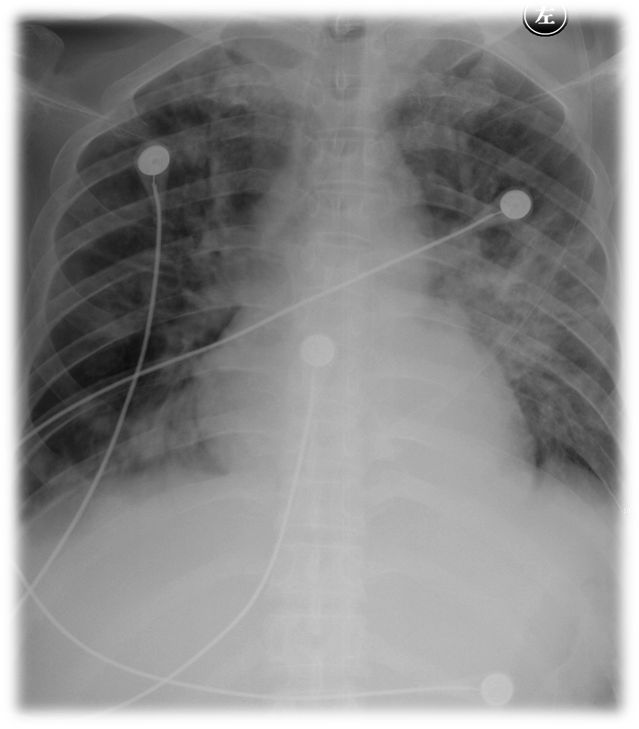

图:患者入院时胸片

42岁的人在短短的几天成了这副模样,没有一个医生敢怠慢,更何况我这个老医生了。先把病史从主管医生那里问了一个底朝天,5天前病人被商场的保安发现昏倒,赶紧叫了救护车,急救人员到现场的时候,病人呼吸、心跳都不好,立即进行了气管插管和用了各种抢救药物,等自主心率稳定了以后,送到了我们这家离病人工作的商场最近的医院。当病人到医院急诊时处在昏迷状态,血压80/50mmHg,心率120次/分,氧饱和度80%,人严重消瘦,双肺听着都是痰鸣音。化验显示白细胞增高,降钙素原到了重度感染的水平;血气提示代谢性酸中毒,PH只有6.8,乳酸数值也不低;血糖达到了25.8mmol/L;胸腹CT发现肺里有明显的渗出病灶和胃、肠道积气。感染中毒性休克,肺部感染,糖尿病可以诊断。接诊医生立即给予了积极的广谱抗生素,呼吸机辅助通气,胃肠减压,补液,控制血糖,血管活性药物维持血压等措施。经过一系列的捆绑治疗,病人的生命体征暂时稳定。可一天后病人的肾功能开始恶化,尿少,肌酐一路飙升,最高到了425μmol/L。血液里的白蛋白也开始急剧下降。此时利尿,白蛋白和血浆的输注哪一个也没敢犹豫。如果肾功能再持续不好转,下一步就需要血液滤过治疗了。由于医疗花销没有减缓的趋势,开始不惜一切代价救治的家属拿不定主意了。